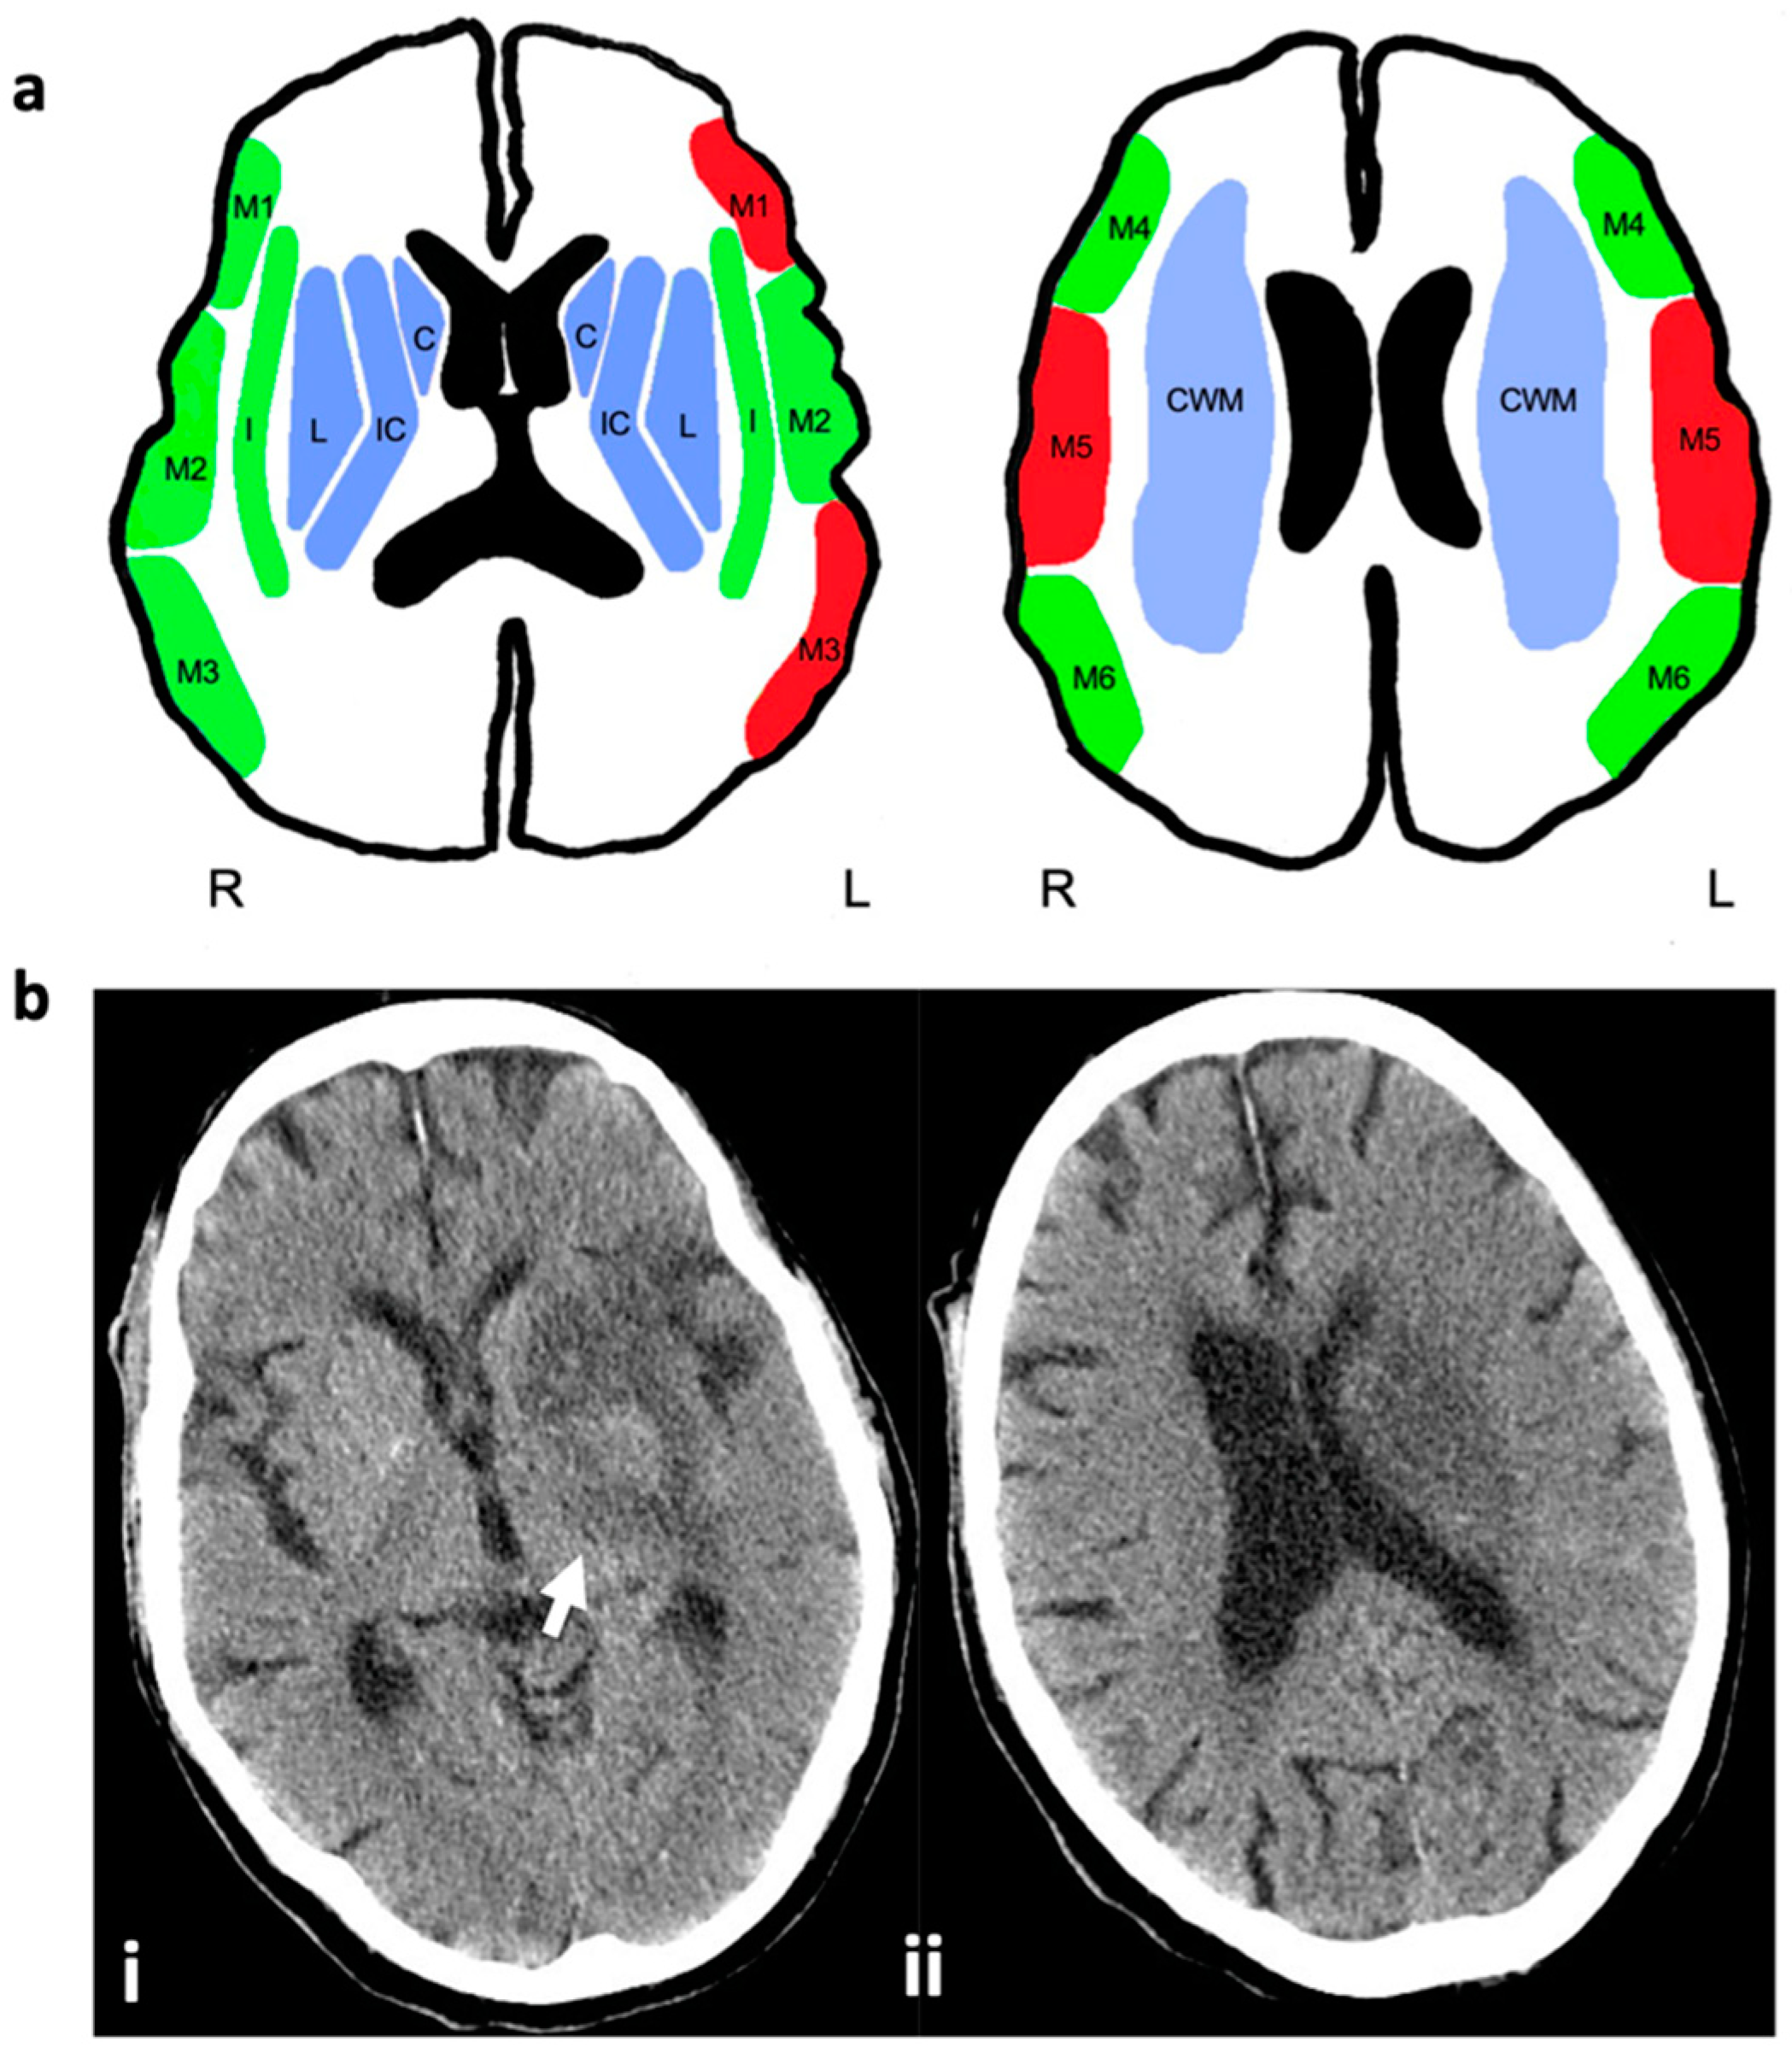

3.2. ASPECTS Score